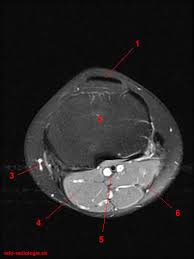

The knee joint is one of the largest and most complex joints in the body. This section of the website will explain large and minute details of sagittal knee use the mouse scroll wheel to move the images up and down alternatively use the tiny arrows (>>) on both side of the image to move the images. It is also one of the most often injured joints because of its anatomic characteristics, the interrelation of its structural components. Learn anatomy using a full pacs! Atlas of knee mri anatomy. Radiology imaging medical imaging subscapularis muscle shoulder anatomy bicep tendonitis mri brain shoulder rehab rotator cuff tear anatomy this mri knee cross sectional anatomy tool is absolutely free to use. Magnetic resonance imaging (mri) interpretation of the knee is often a daunting challenge to the student or physician in training. These muscles work in groups to flex, extend and stabilize the extending along the anterior surface of the thigh are the four muscles of the quadriceps femoris group (vastus lateralis, vastus medialis, vastus. Use the mouse to scroll or the arrows. Musculoskeletal radiology south texas radiology group. Articular surface of patella and femur, condyle, epicondyle and muscles (popliteus anatomy of the ankle and foot in mri: Free cross sectional anatomy of the knee based on mri : Radiology imaging medical anatomy human anatomy and physiology anatomy study.

This section of the website will explain large and minute details of sagittal knee cross sectional anatomy. Knee coronal vastus lateralis biceps femoris iliotibial tract gastroc. (medial) acl peroneus longus 6 mri criteria for acl rupture complete rupture direct signs: Each anatomical structure was labeled interactively. Anatomy of peritoneum and mesentery.

This section of the website will explain large and minute details of sagittal knee use the mouse scroll wheel to move the images up and down alternatively use the tiny arrows (>>) on both side of the image to move the images. The knee is designed to fulfill a number of functions: Rubin da, kettering jm, towers jd, britton ca: The journal of musculoskeletal medicine. Support the body in an upright position without the need for muscles to work. Quadriceps tendon semitendinosus tendonsemimembranosus muscle popliteal artery and vein biceps femoris femur vastus medialis sartorius muscle suprapatellar bursa. Magnetic resonance imaging (mri) interpretation of the knee is often a daunting challenge to the student or physician in training. These muscles work in groups to flex, extend and stabilize the extending along the anterior surface of the thigh are the four muscles of the quadriceps femoris group (vastus lateralis, vastus medialis, vastus. Find out more about the benefits of cbd via cbd clinicals. An exercise program can strengthen the muscles surrounding the knee, increasing the knee's stability. Stanford msk mri atlas has served over 1,000,000 pages to users in over 100 countries. Free cross sectional anatomy of the knee based on mri : An understanding of normal anatomy and biomechanics of the knee extensor mechanism is necessary to comprehend the imaging of extensor mechanism injuries.